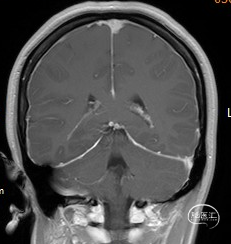

图1:冠状位MRI提示硬脑膜弥漫性增强。